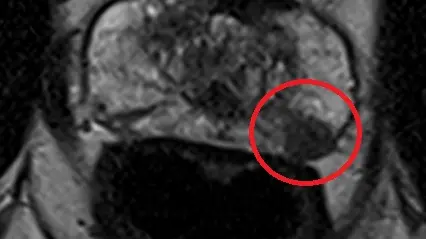

Prostatacarcinom (PIRADS4-Befund)

Kontrastmitteldynamik

Die Untersuchung umfasst verschiedene Bildsequenzen (=multiparametrisch), darunter:

• hochauflösende T2w- Aufnahmen (Beurteilung der Anatomie)

• diffusionsgewichtete Sequenzen (Beurteilung der Zelldichte)

• dynamische Kontrastmittelaufnahmen (Beurteilung der Durchblutung)

Diese Kombination ermöglicht eine sehr genaue Beurteilung nach international anerkannten Kriterien (PIRADS-Befundungsschema).